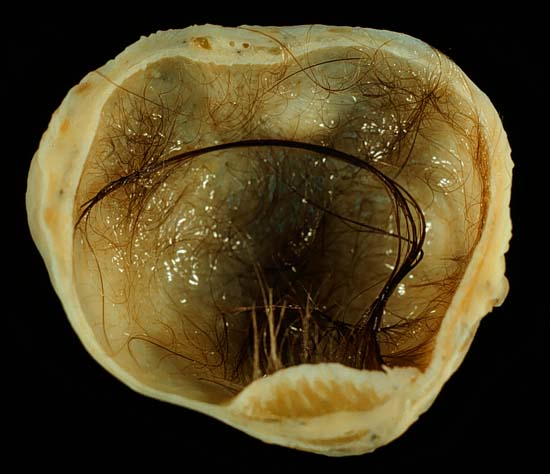

A dermoid cyst is a teratoma of a cystic nature that contains an array of developmentally mature, solid tissues. It frequently consists of skin, hair follicles, and sweat glands, while other commonly found components include clumps of long hair, pockets of sebum, blood, fat, bone, nail, teeth, eyes, cartilage, and thyroid tissue.

While all ovarian cysts can range in size from very small to quite large, dermoid cysts are not classified as functional cysts. Dermoid cysts originate from pluripotent germ cells (which are present at birth) that differentiate abnormally, developing characteristics of mature dermal cells. Complications exist, such as torsion (twisting), rupture, and infection, although their incidence is rare. Dermoid ovarian cysts which are larger present complications which might require removal by either laparoscopy or laparotomy (traditional surgery). Rarely, a dermoid cyst can develop in the vagina.